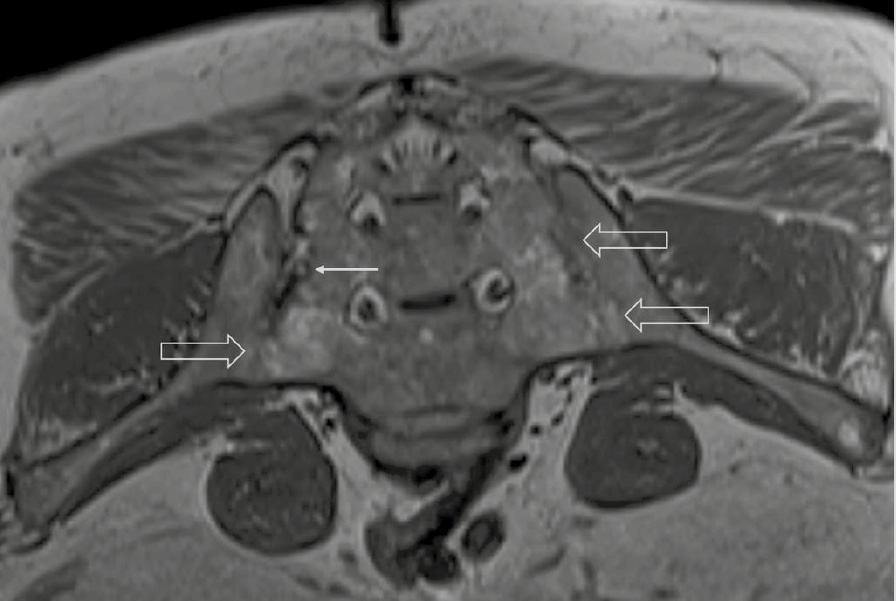

При компьютерной томографии органов грудной клетки данных за «свежие» очаговые и инфильтративные изменения не получено. Увеличения лимфатических узлов подмышечных областей, средостения, корней легких не выявлено. Отмечался усиленный грудной кифоз, обызвествление передней продольной связки, на всем уровне исследования определялись передне-боковые спондилофиты, а также анкилоз большинства реберно-поперечных суставов. По данным рентгенографии кистей (рис. 1, 2) и стоп (рис. 3, 4) диагностированы признаки эрозивного артрита, анкилоз суставов запястья. По данным МРТ крестцово-подвздошных суставов (КПС) определялся неравномерный анкилоз КПС, хрящи по суставным поверхностям неравномерной толщины, примерно на половине протяжении сустава отсутствуют, «суставной промежуток» облитерирован. Неравномерность и нечеткость контура суставных поверхностей за счет множества краевых эрозий справа, единичных – слева, с наличием остеокластоза, в нижнем отделе слева по смежным отделам определяются участки трабекулярного отека, данная находка клинически интерпретирована как двусторонний активный сакроилиит (рис. 5, 6).

Рис. 2. Рентгенограмма правой кисти в прямой проекции. Краевая эрозия суставной поверхности лучевой кости (тонкая стрелка), множественные анкилозы суставов запястья (толстые стрелки)

В возрасте 40 лет присоединились жалобы на симметричные воспалительные боли в лучезапястных суставах и мелких суставах кистей, резкое снижение объема движения в лучезапястных суставах. При осмотре пациента выявлено: число болезненных суставов – 7, число припухших суставов – 4, положительный симптом поперечного сжатия кистей и стоп, ульнарная девиация мелких суставов стоп. Резко сниженный объем движения в лучезапястных суставах обеих кистей. По данным рентгенологического обследования зафиксированы типичные изменения для РА: резкое неравномерное выраженное сужение суставных щелей, субхондральный склероз в лучезапястных суставах, анкилоз в суставах запястья, пястно-запястных, пястно-фаланговых и межфаланговых суставах. Краевые эрозии оснований основных фаланг двух пальцев; участки кистовидной перестройки костной ткани. Локальное утолщение мягких тканей. При лабораторном обследовании пациента отмечен положительный ревматоидный фактор, высокий титр антицитруллинированных антител, повышение острофазовых белков.